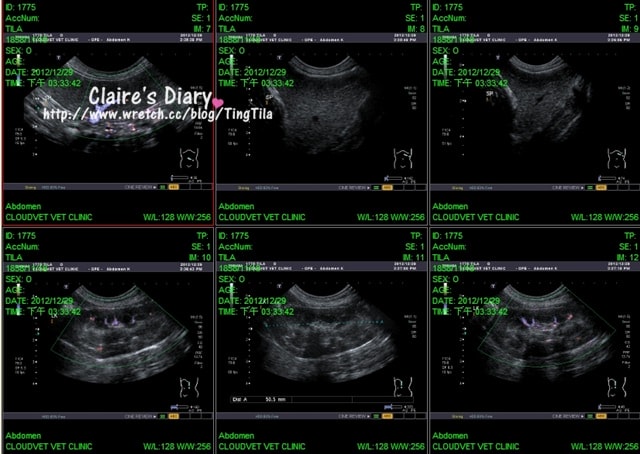

((超音波截圖一共30張!!))

(每張縮圖的右下角,都有正在照抄音波的部位只是))

超音波的部份,腹腔的血流比較低~50

大部分的狗都是80-90

TILA比較慢的原因,不是心臟沒有力氣

而是血液比較黏稠

想像水清澈的時候是不是流的比較快,水稠稠的時候就會較緩慢

醫生說如果在他不知道TILA今天的驗血結果情況下

看到這樣的血流速度,會判斷TILA是否心臟有問題

但是心臟在超音波下與X光下都是OK的!所以是血液濃稠的關係

脾臟都正常,要看脾臟有無異常是觀察脾臟的尾端

TILA的脾臟尾端看起來是很銳利的形狀~這很好

但如果今天照抄音波發現脾臟的尾端變成鈍圓的形狀!就要注意啦~~

而TILA的脾臟比一般的狗狗大一點

但是就TILA自己本身而言~這個脾臟是正常的!!

在腎臟的部份,超音波照的比較久

這是因為TILA有多血症的關係,所以要觀看她血液的透析是否良好

如果黏稠就會通過的比較差,但整體看下來~都很順!還好^^

腎上腺也都正常4.4OK!!